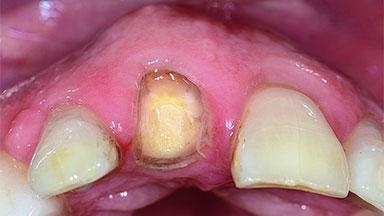

A 49-year-old female patient was referred for implant therapy to replace the upper right central incisor (tooth 11). The tooth had been assessed by an endodontist who diagnosed a vertical fracture of the root. The tooth had a hopeless prognosis and needed to be extracted. The patient was healthy and was not taking any medications. She was allergic to penicillin. The patient had high esthetic demands but her expectations were realistic. The extraoral examination revealed no facial asymmetries. The right temporomandibular joint demonstrated an opening click but was otherwise asymptomatic. The lip line was high with a significant gingival display.

Shape of Tooth Crowns Rectangular Triangular

Width of Edentulous Span 1 tooth (>= 7 mm) 1 tooth (< 7 mm) 2 teeth or more

Mesio-Distal Space Symmetry +/- 1 mm of contra-lateral tooth